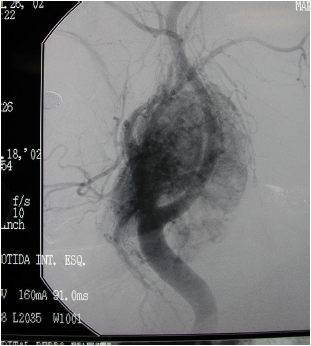

Paciente relata crescimento de tumoração na região cervical. Realizou o exame que evidenciou a lesão abaixo.

Enunciado 740291-1

A hipótese diagnóstica é: